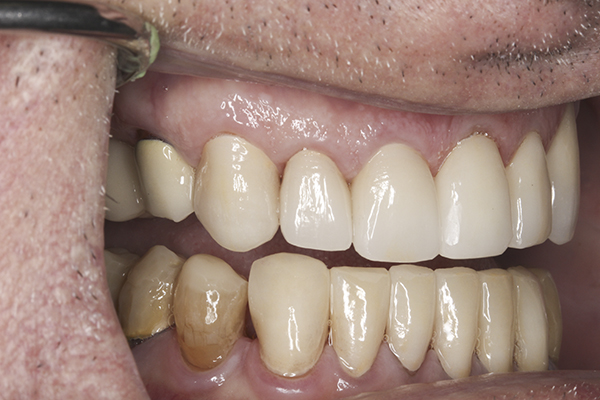

(9.) Preoperative right lateral, closed view.

Figure 9

(10.) Preoperative anterior, closed view. Note the end-to-end occlusion of the anterior teeth and the wear on the incisors and centrals resulting in no anterior or canine guidance.

Figure 10

(11.) Preoperative left lateral, closed view.

Figure 11